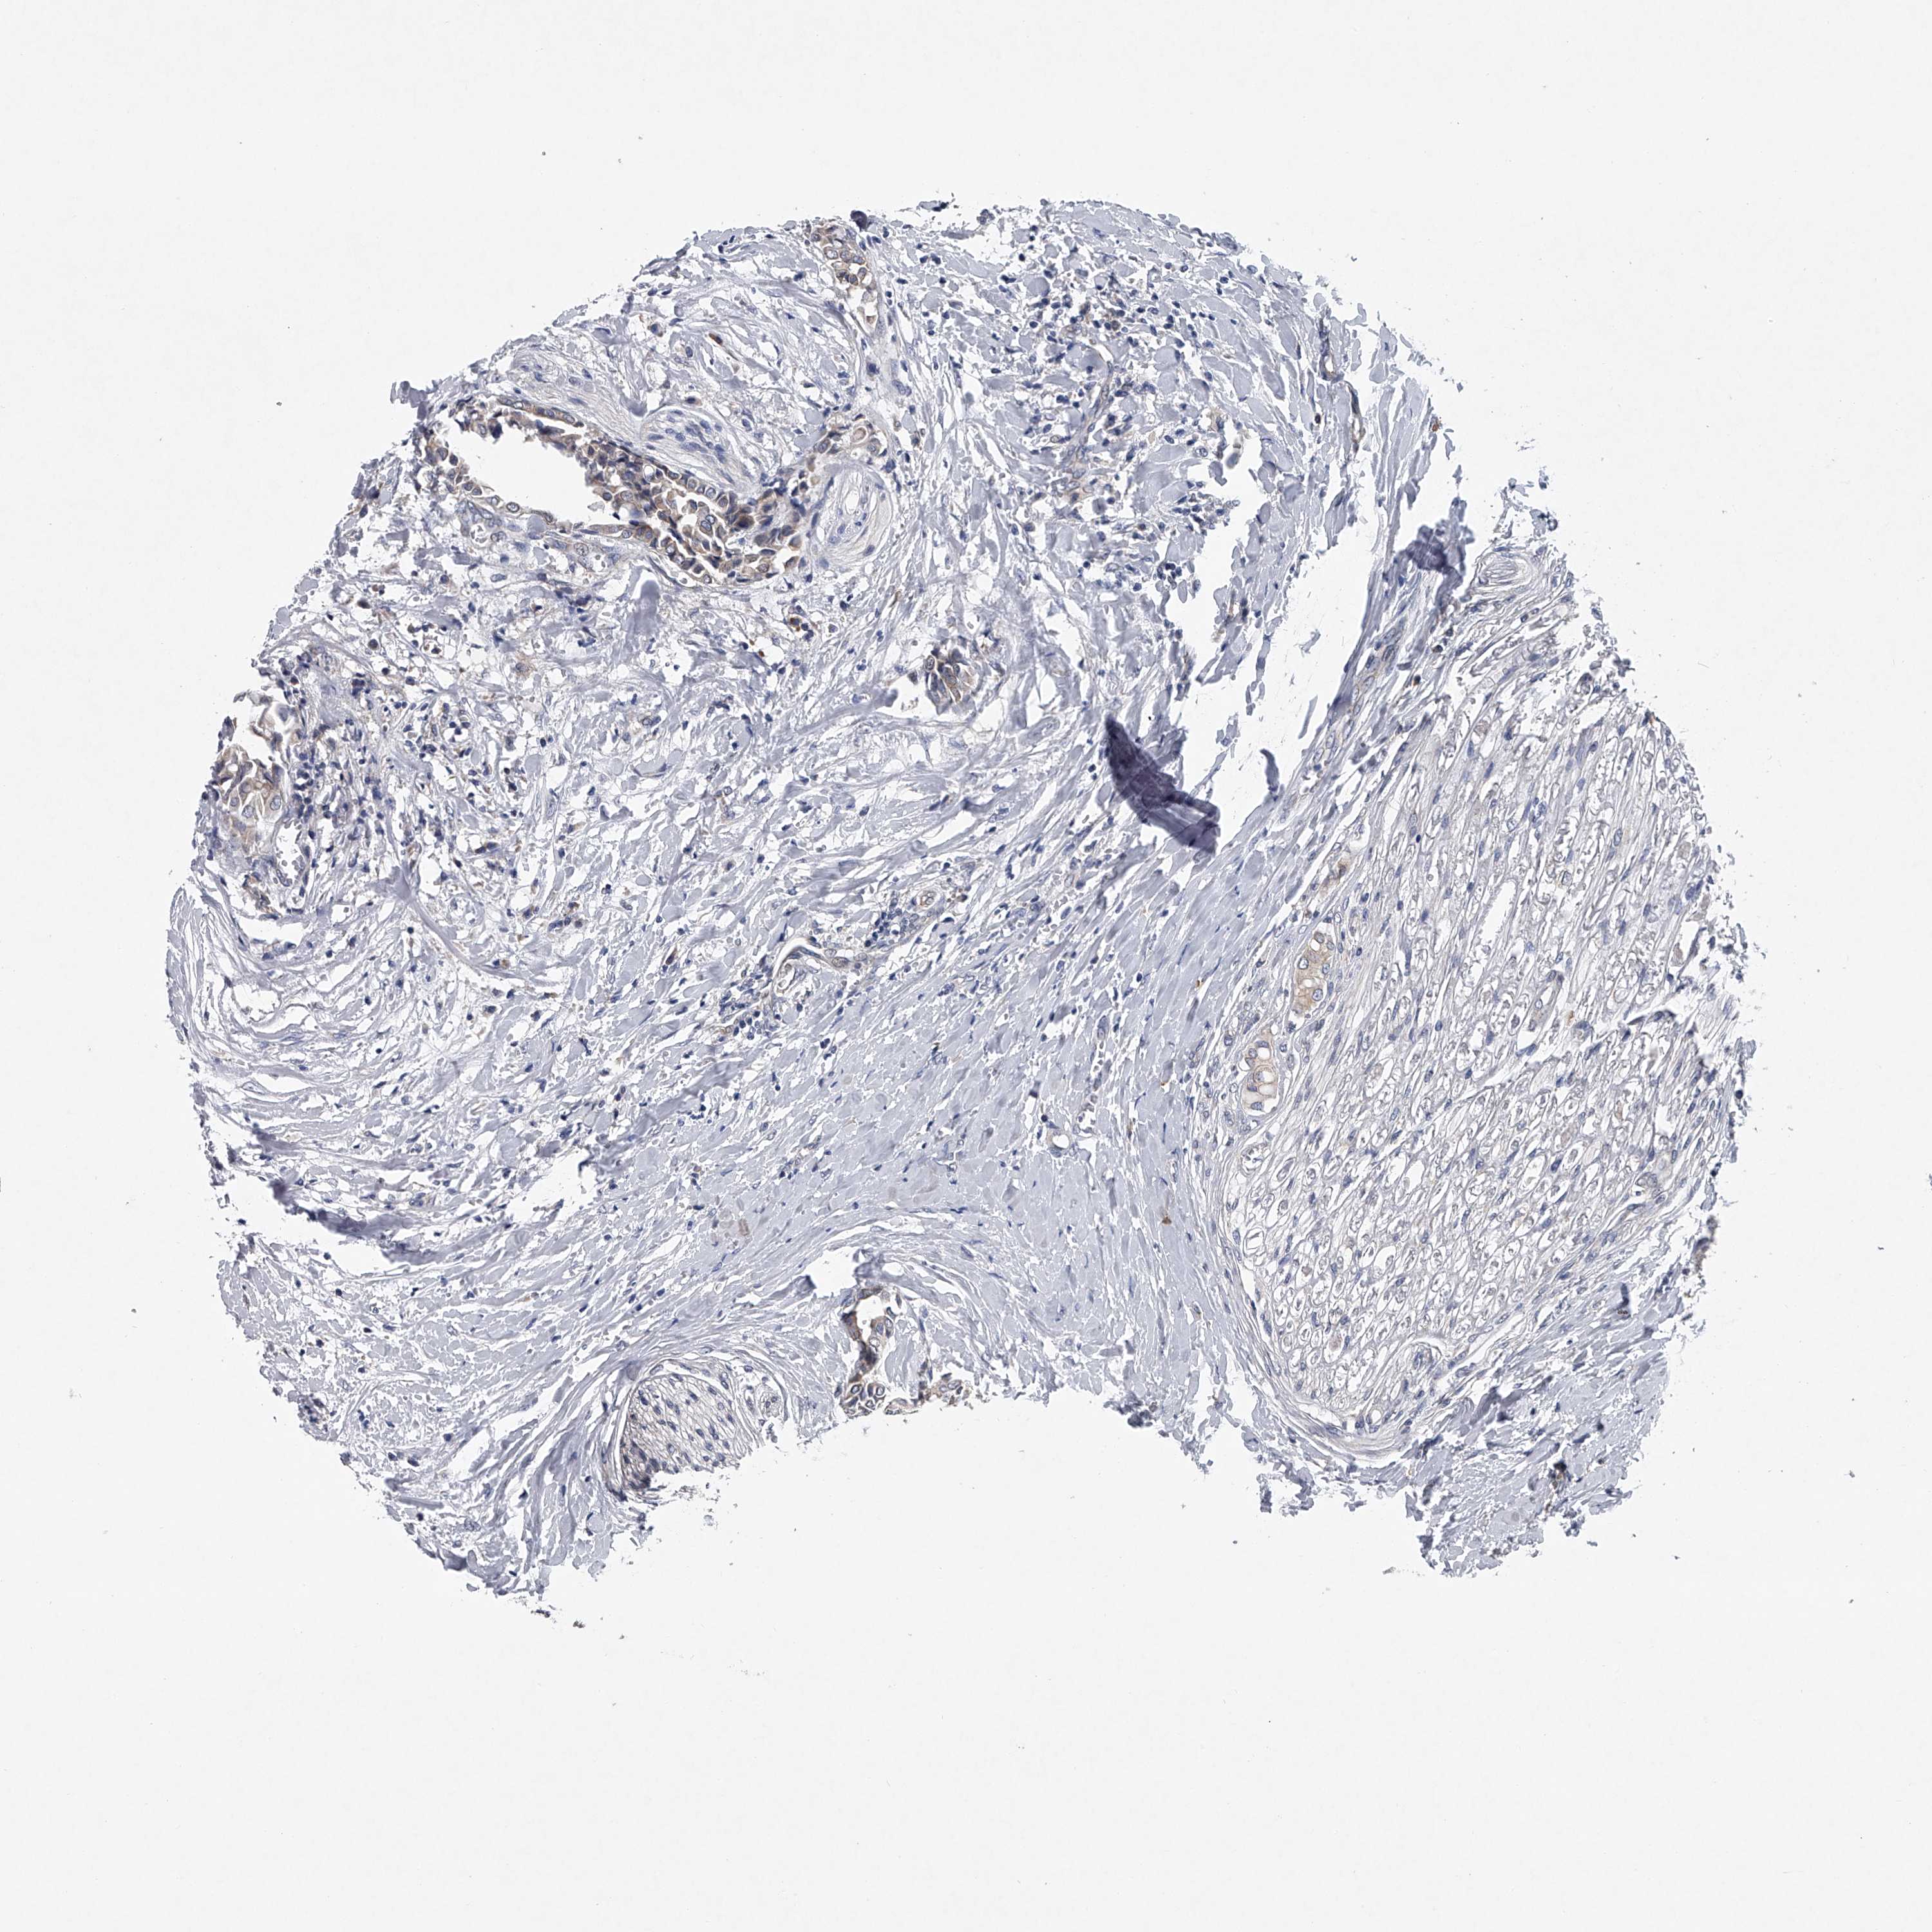

HEAD AND NECK CANCER - Protein expressioni

A mouse-over function shows sample information and annotation data. Click on an image to view it in a full screen mode. Samples can be filtered based on level of antibody staining by selecting one or several of the following categories: high, medium, low and not detected. The assay and annotation is described here.

Antibody stainingi

Antibody staining in the annotated cell types in the current human tissue is reported as not detected, low, medium, or high, based on conventional immunohistochemistry profiling in selected tissues. This score is based on the combination of the staining intensity and fraction of stained cells.

Each image is clickable and will lead to virtual microscopy that enables deeper exploration of all samples and also displays staining intensity scores, fraction scores and subcellular localization as well as patient and tissue information for each sample.

Antibody CAB034107

Squamous cell carcinoma, NOS

Squamous cell carcinoma, metastatic, NOS

Adenocarcinoma, NOS

Adenoma, NOS